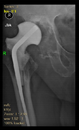

The guiding wire was inserted and controlled with fluoroscopy flashes (Figure 4). The drilling and reaming were carried out in accordance with the recommendations:

Figure 4.

The biocompatible aiming device after insertion of the guiding wire.

The radiological examination allowed us to verify the close bone-to-implant contact and the unchanged position of the implant during follow-up.

In all the cases operated with the above-described targeting procedure, the stems of the cups remained between the cortical bone surfaces without perforation of the linea terminalis, as shown by postoperative radiographs. There were no complicated surgical situations. In 16 cases, the wound healings were uneventful, and the hips were able to bear weight again after postoperative rehabilitation.